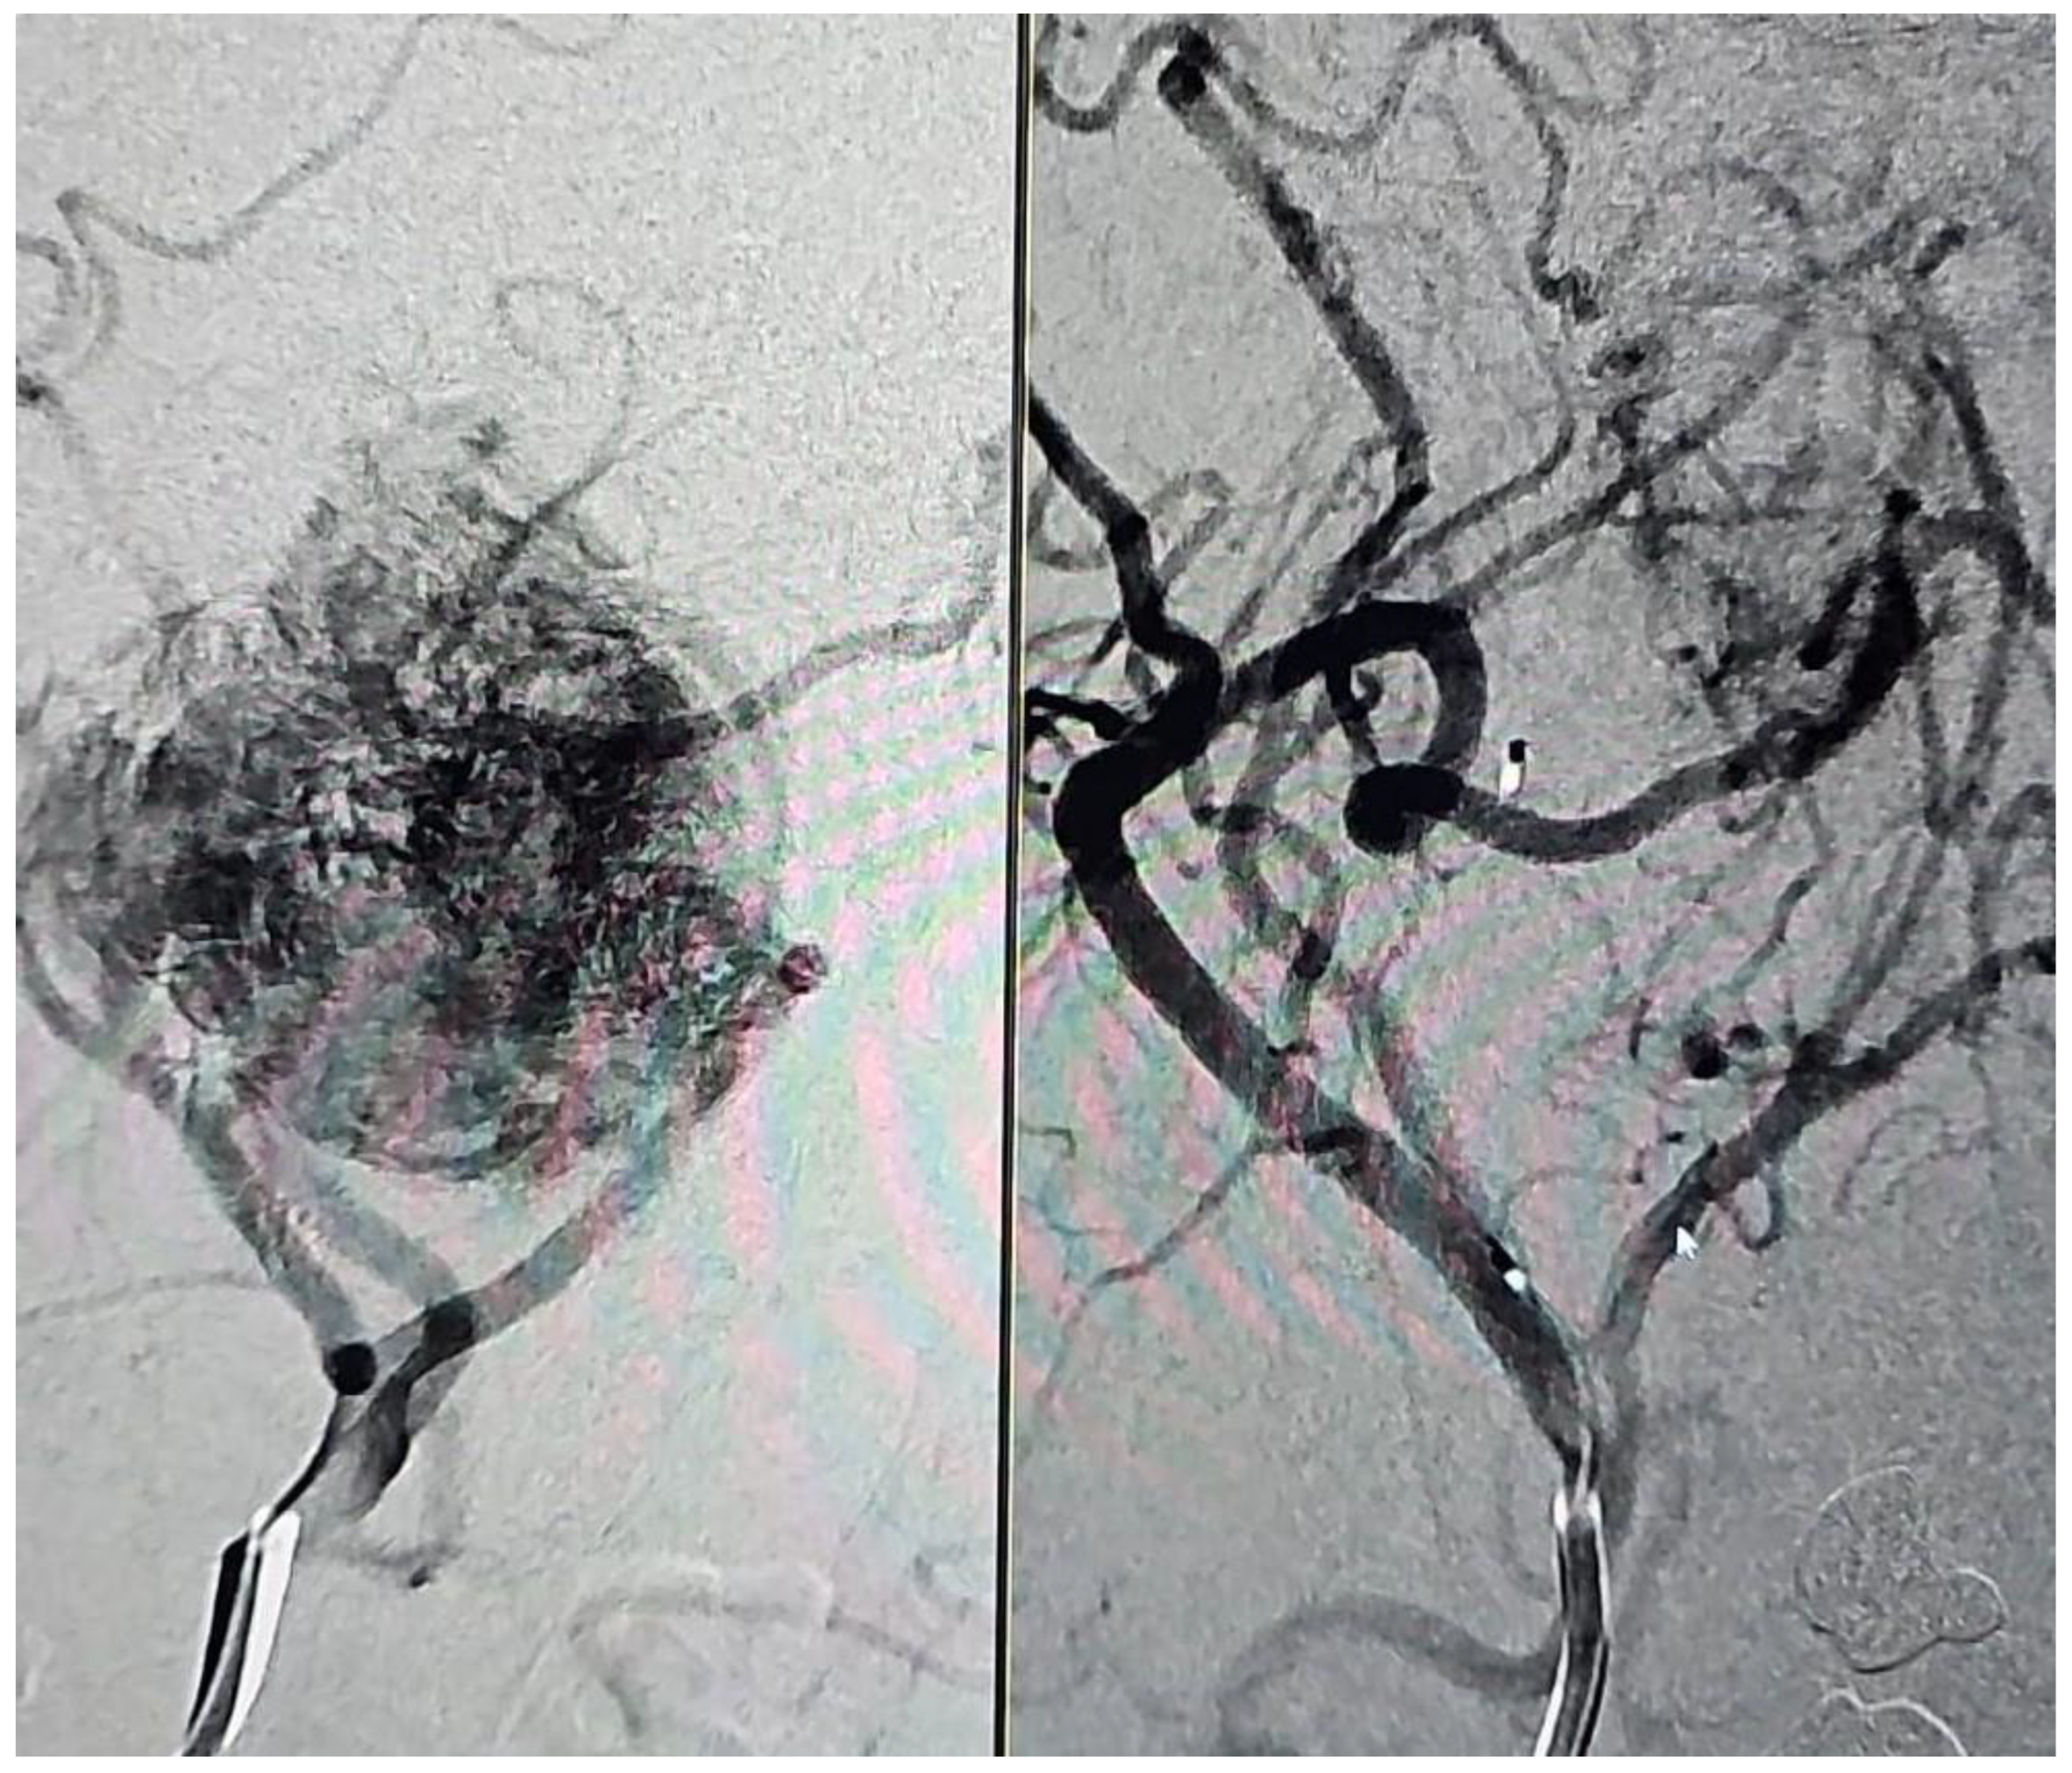

2.4. Angiographic Evaluation

3.4. Primary Outcome: Effectiveness of Embolization

4.1. Embolization with Onyx

4.2. Particle Embolization